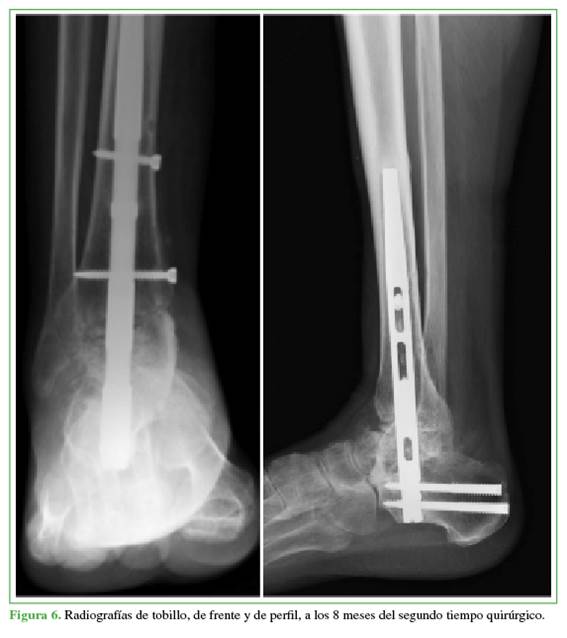

Se observó la consolidación completa a los 12 meses de la cirugía (Figura 6). El protocolo de rehabilitación consistió en seis meses sin carga inmovilizado con bota walker y carga parcial asistida con bota walker y dos muletas a los seis meses del segundo tiempo quirúrgico.